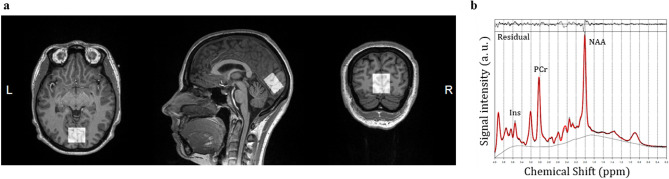

In dataset 1, brain MRI was performed on a 3 T MRI scanner (Siemens Magnetom Prisma-fit Syngo MR D13D, Erlangen, Germany). Data on four cerebral small vessel disease features are available, i.e., total brain parenchyma volume, white matter hyperintensity volume, and presence of lacunar infarcts and cerebral microbleeds35. (Supplementary Information). In dataset 2, subjects were studied with a 3 T MRI scanner (Siemens Magnetom Skyra fit (Siemens Healthcare, Erlangen, Germany). Subjects were positioned supine inside the MRI and the head was immobilized with foam inserts on top of a radiofrequency probe. For signal acquisition, a 20-channel Head/Neck coil was used. After taking brain morphology scans, 1H-MRS spectrum was measured from a 20 × 30 × 30 mm voxel in the occipital lobe using PRESS sequence with 176 water-suppressed signal averages and 4 signal averages without water suppression. The occipital lobe was selected due to its reliability for spectral acquisition36. The voxel was carefully placed in the center of the occipital lobe, making sure that the margins of the voxel would not be close to the skull or the cerebellum (Fig. 1a). The measurement lasted 10 min. The sequence parameters were repetition time = 3000, echo time = 35 ms, bandwidth = 2000 Hz. Water suppression was performed using the CHESS method. Figure 1b shows a representative example of a fitted spectrum.

Figure 1.

Voxel placement for 1H MRS in the occipital lobe (a), and a representative example of a fitted spectrum (b).